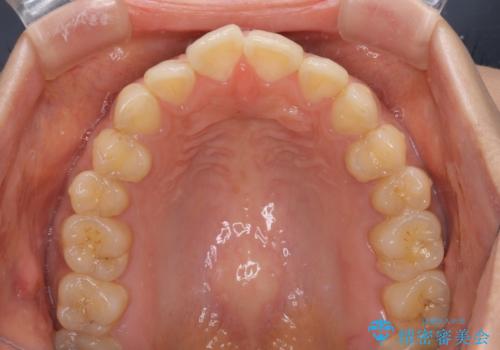

- 前歯のデコボコと上下前歯の隙間を気にして来院された患者様です。

下顎前歯はデコボコのため、歯肉が腫れやすくなっていました。

また、舌突出癖のため、上下前歯の間に隙間ができてしまい、上顎前歯が前方に傾斜している状態でした。

舌突出癖改善のためのトレーニングを行いながら、インビザラインにて矯正治療を行うこととしました。

舌のトレーニングをしっかりと行っていただき、上下前歯をしっかりと接触させることができました。

咬合力が強いため、治療途中に奥歯が咬み合わない期間が続きましたが、上下の奥歯でゴムかけを行っていただき、違和感なく咬み合うように仕上げることができました。